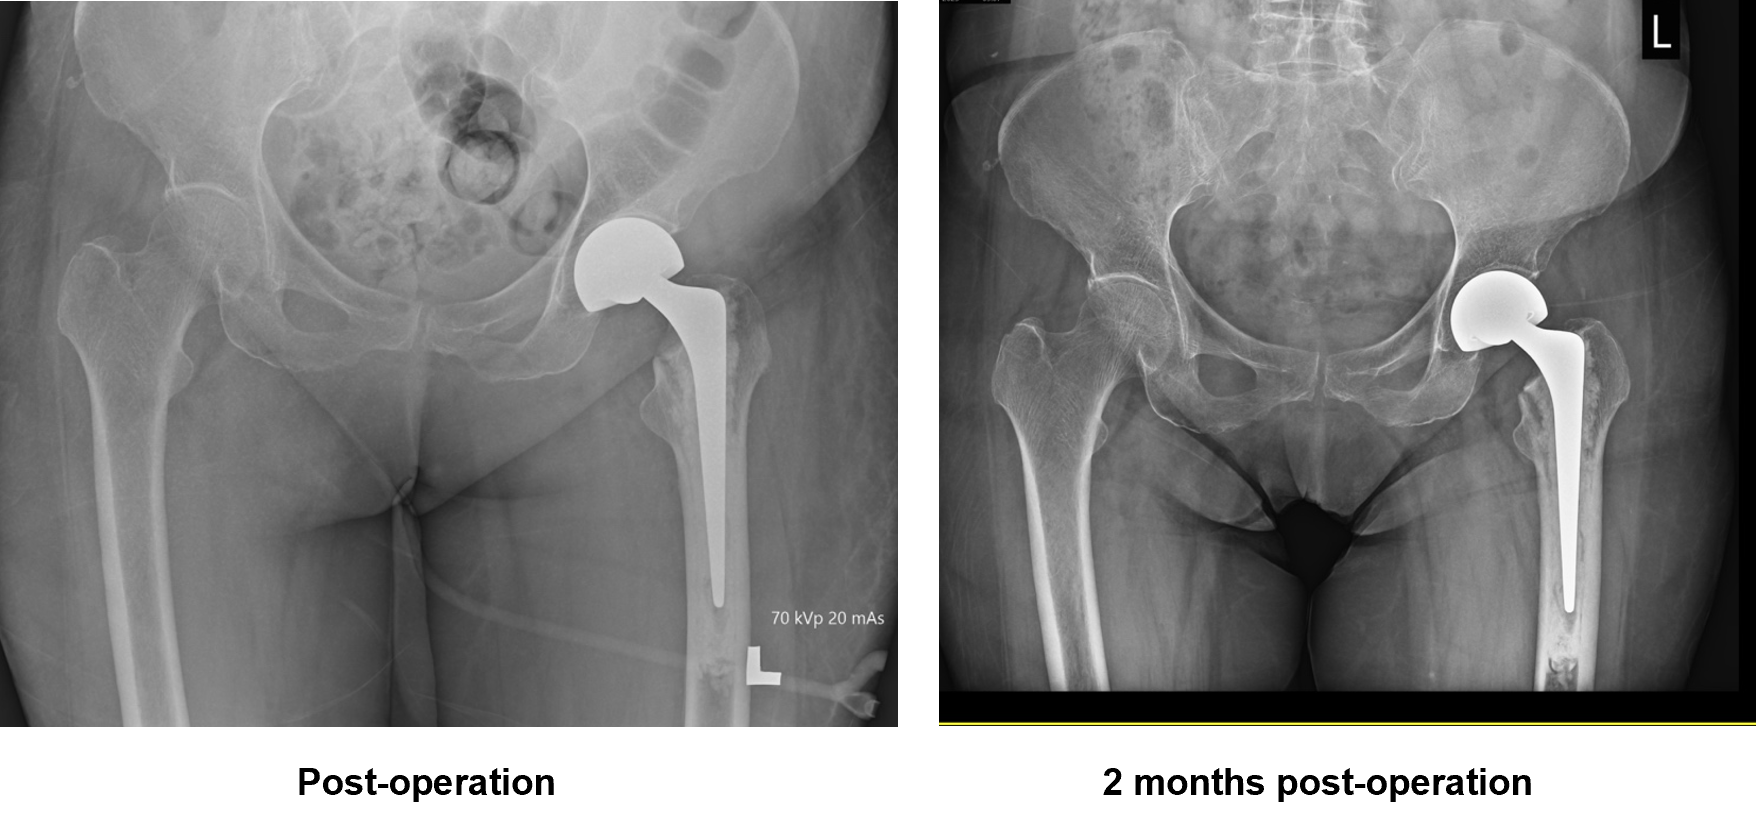

- Left bipolar hemiarthroplasty

The patient was able to ambulate without support 1-month post-surgery.

- The 1st DXA Scan of hip and spine was performed after the left hip surgery.